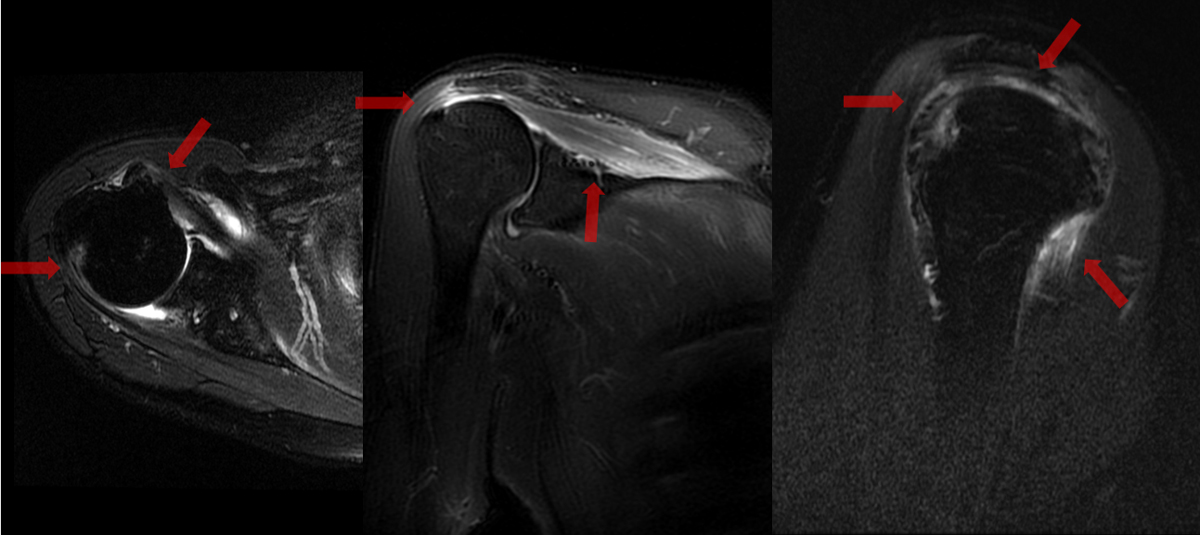

- STIR

棘上筋腱、棘下筋腱、肩甲下筋腱に付着部炎

棘上筋の炎症

大結節のエロージョン

- 【脊椎関節炎(SpA)での肩関節病変】

腱板炎、大結節(腱付着部)のエロージョン、付着部の骨髄浮腫が特異的所見である。

関節包周囲軟部組織の浮腫および造影効果は関節リウマチより高度である。

反応性関節炎は下肢優位の病変分布とされているが、肩関節病変をきたすこともある。